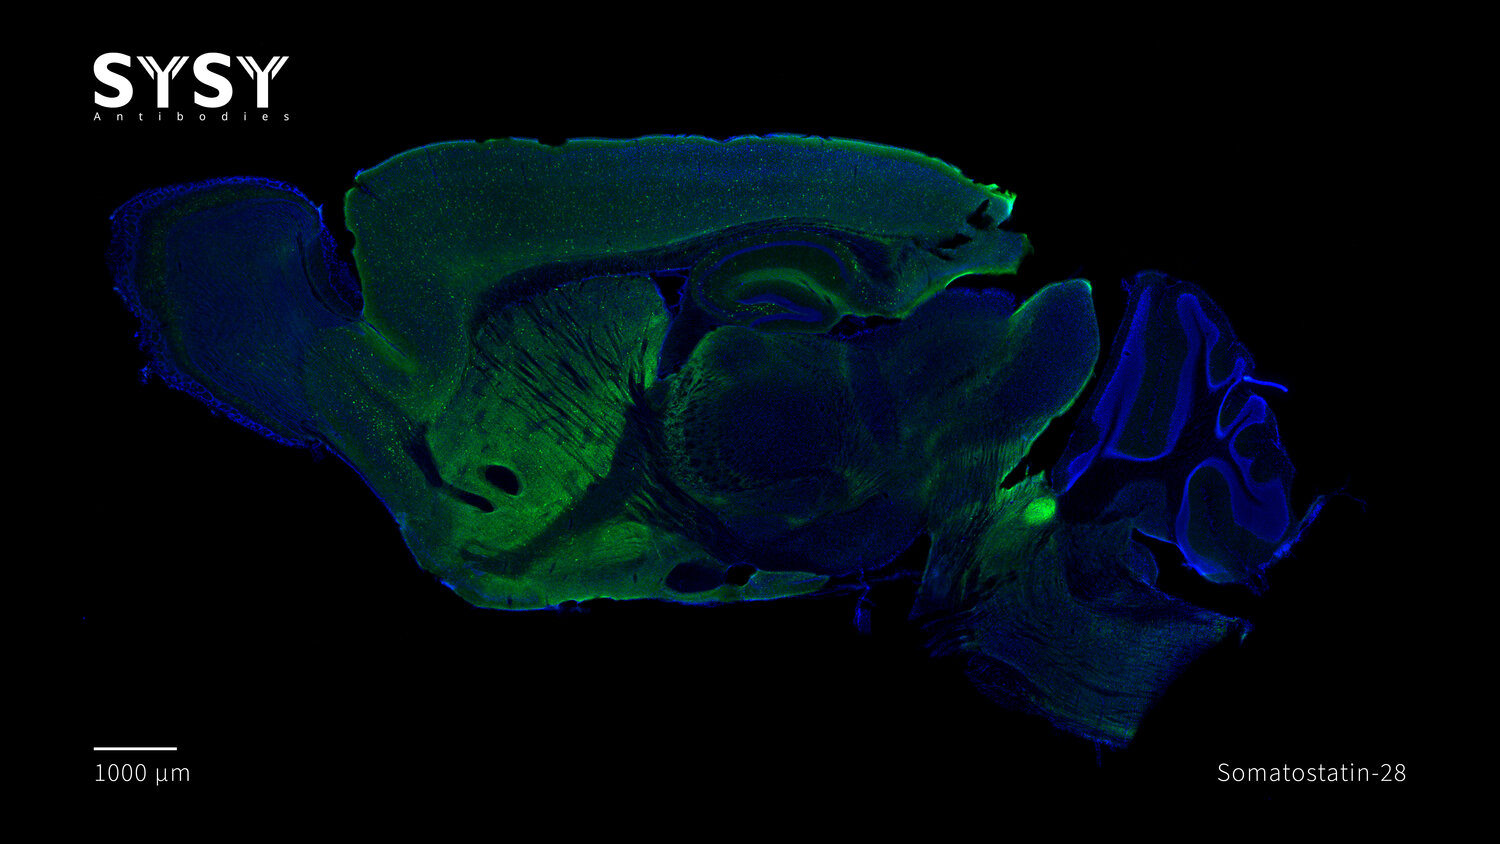

Somatostatin-28 antibody - 366 017

ICC: 1 : 500 up to 1 : 2000 gallery

IHC: 1 : 500 up to 1 : 1000 gallery

IHC-P: 1 : 100 up to 1 : 1000 gallery

Specificity The antibody detects somatostatin-28. It also recognizes the unprocessed precursor protein. It does not bind to somatostatin-14.